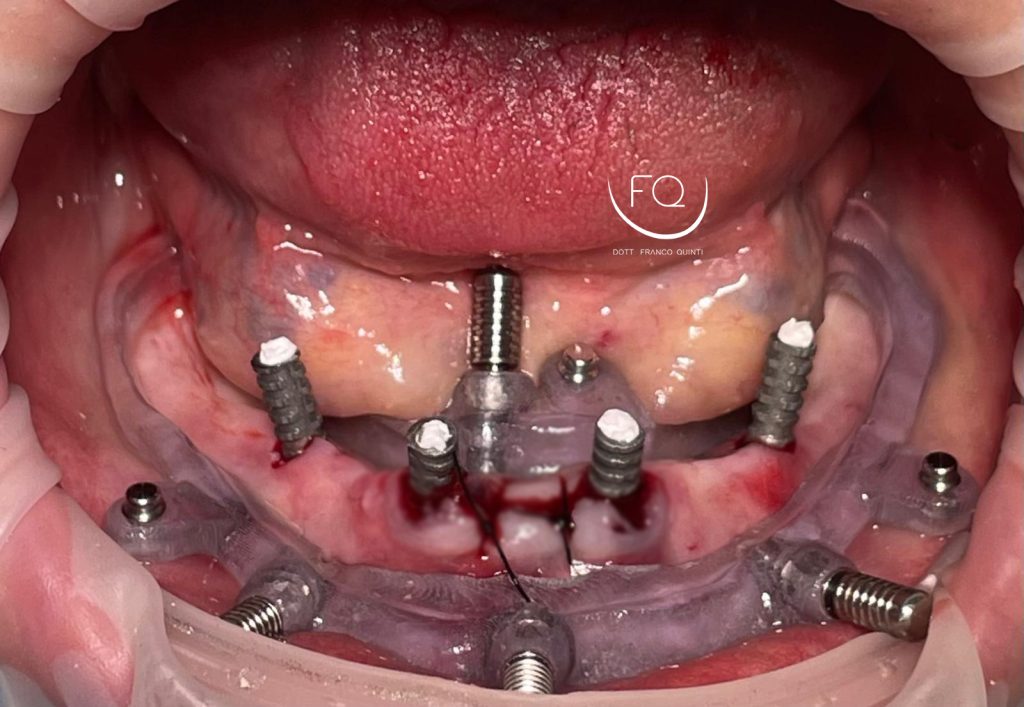

Oggi vi presento un caso di riabilitazione dell’arcata inferiore eseguito con l’utilizzo di dime scomponibili.

Il trattamento ha previsto l’inserimento di 4 impianti Prama Power di Sweden & Martina e la contestuale riabilitazione protesica provvisoria. Tra 3 mesi il caso verrà finalizzato con una protesi definitiva.